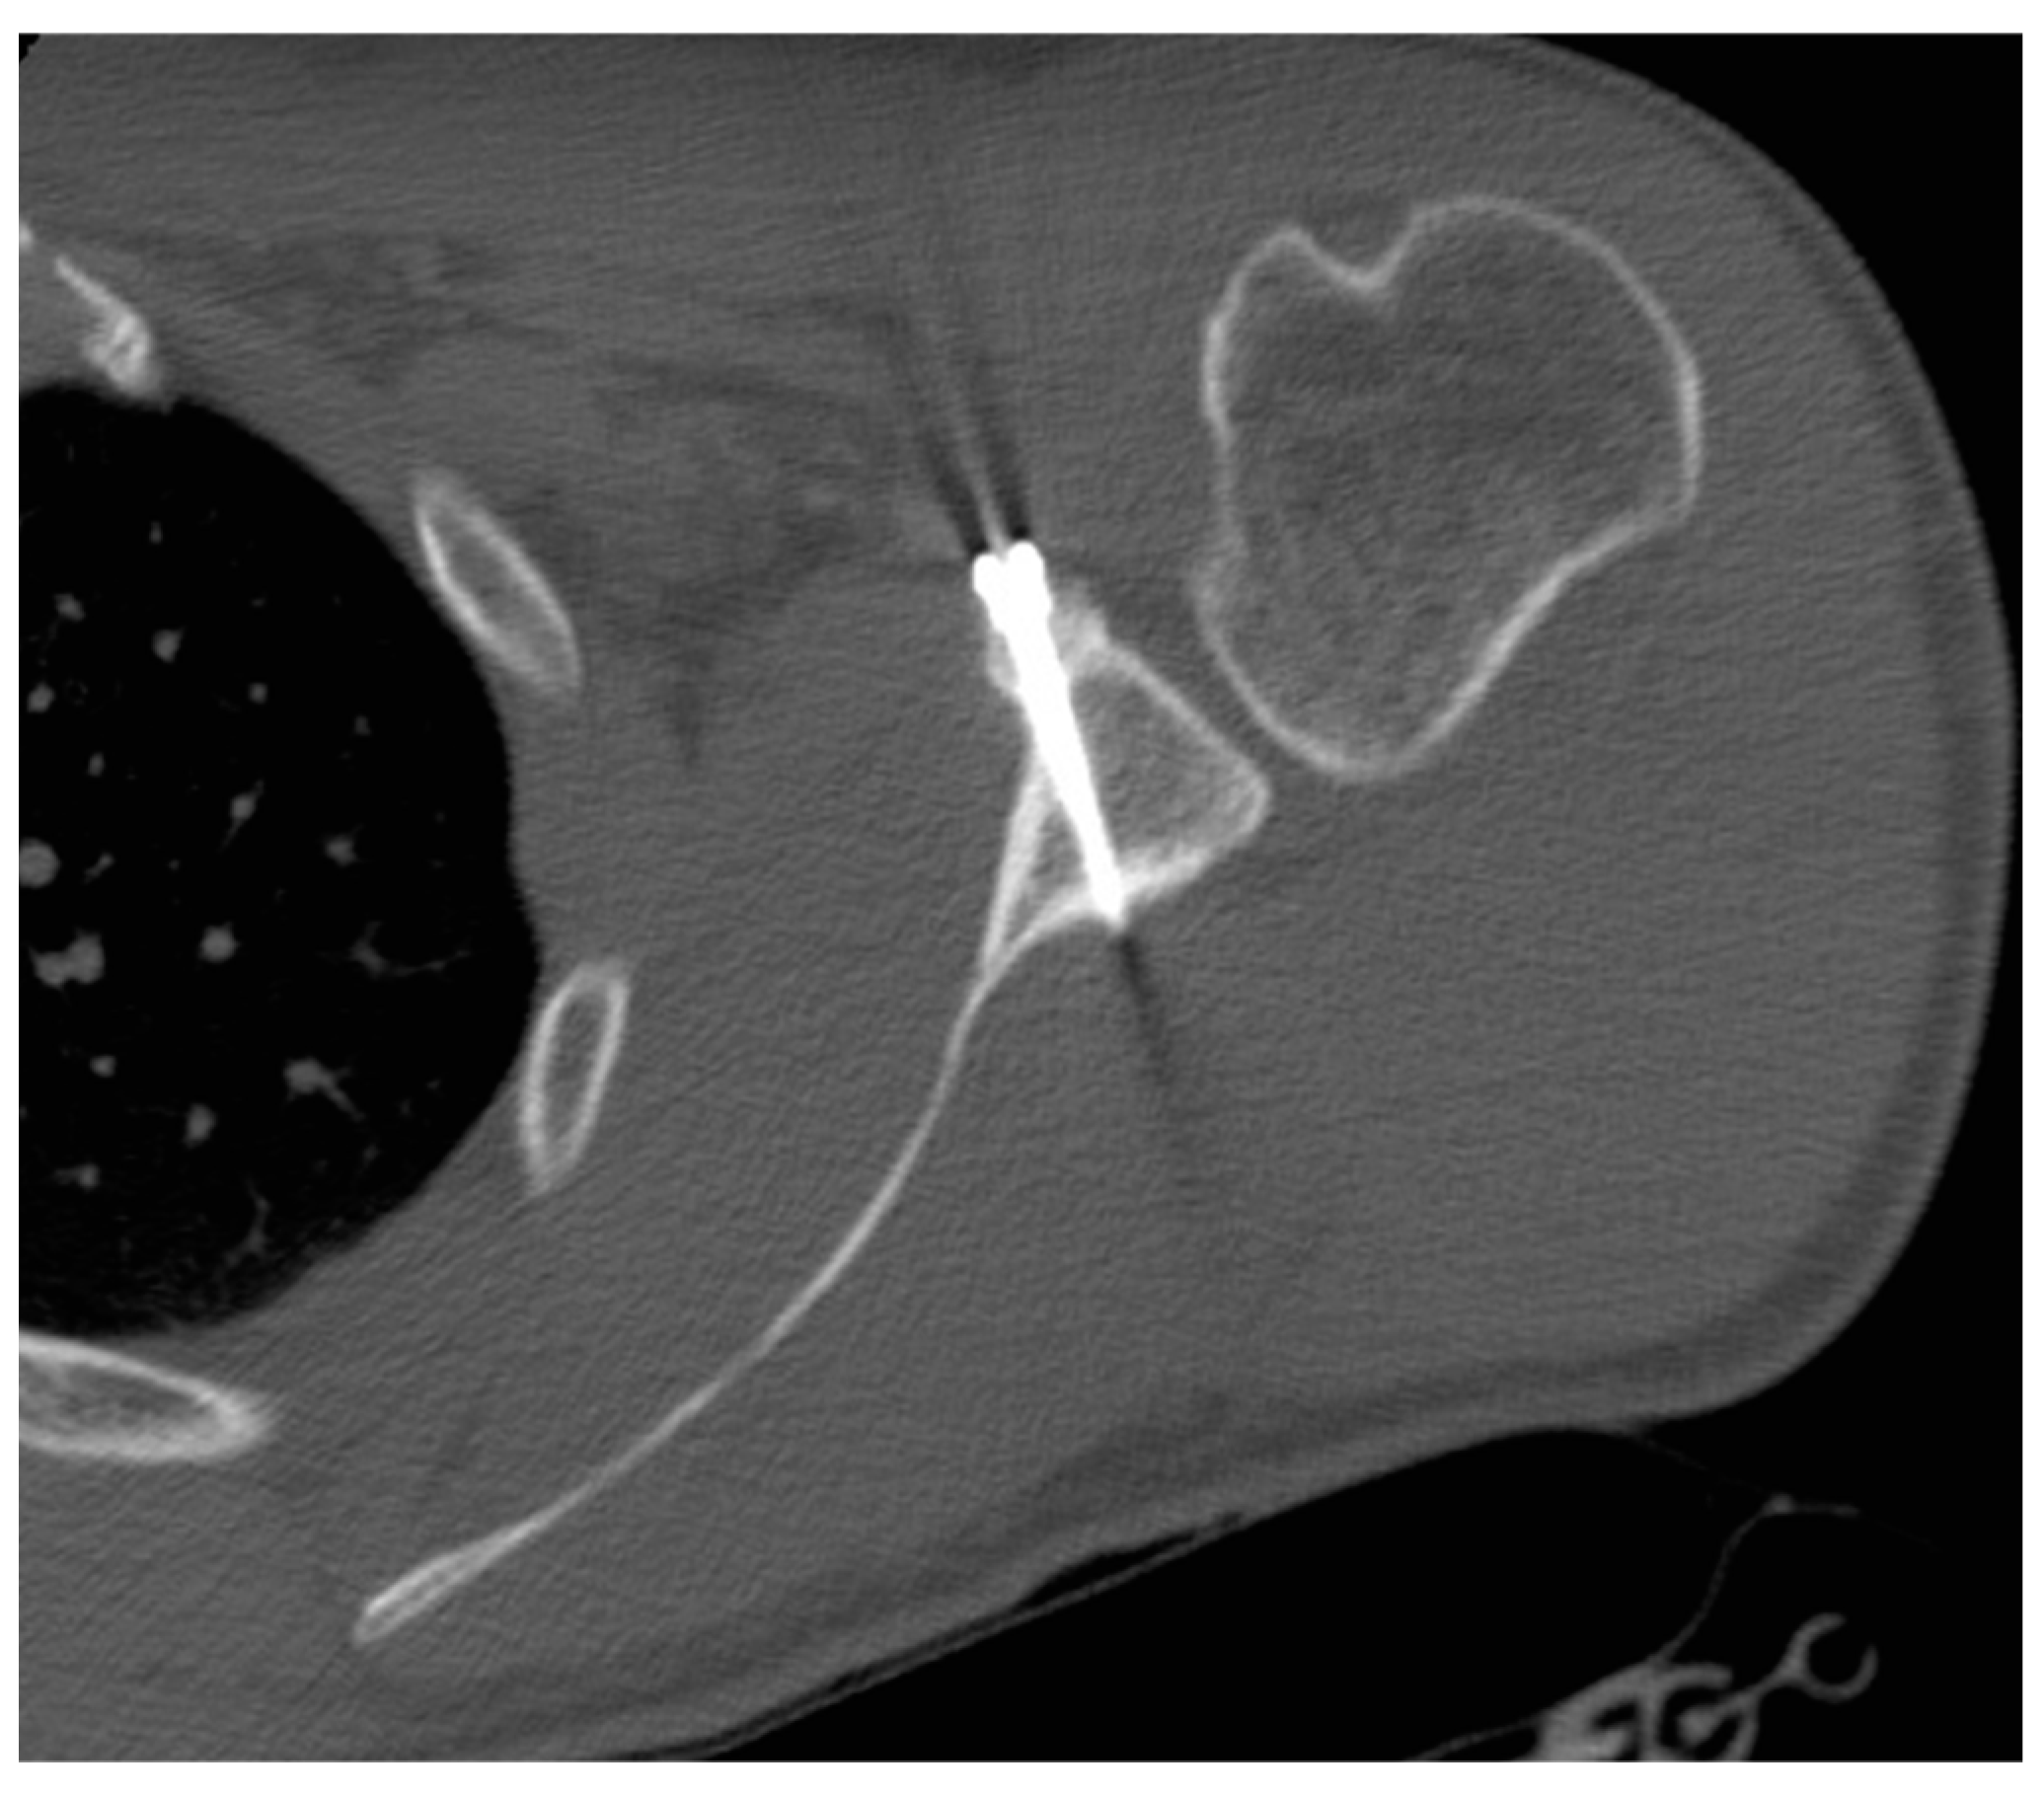

3.3.3. Screws Angle